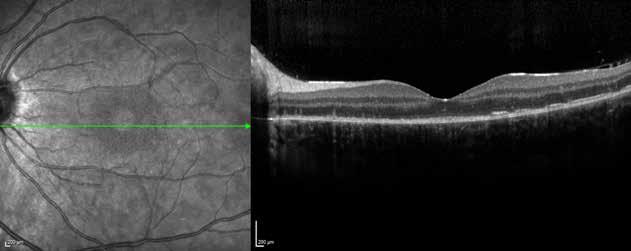

Type 1 MNV is characterized by the growth of vessels from the choriocapillaris into the subRPE space. On fluorescein angiography (FA), Type 1 MNV commonly presents late leakage of undetermined source, defined as areas of leakage at the level of the retinal pigment epithelium in the late phase of the angiogram without well-demarcated areas of hyperfluorescence in the early phase of the angiogram that would explain the leakage. It may also appear as fibrovascular pigment epithelial detachment, defined as areas of irregular retinal pigment epithelium elevation detectable on stereoscopic angiography. As a result, Type 1 MNV was originally termed occult neovascularization.3 Indocyanine green angiography (ICGA) should be used to visualize part of the vascular structure but it often reveals only late staining of the lesion, referred to as a plaque.4 (Figure 1)

1. Multimodal imaging of Type 1 macular neovascularization. Fundus autofluorescence (A) showing fine alteration of retinal pigment epithelium. Late phase (B) of fluorescein angiography revealing pinpoints of hyperfluorescence. Both early (C) and late phases (D) of indocyanine green angiography reveal a central hyperfluorescent zone, indicative of type 1 macular neovascularization, consistent with optical coherence tomography angiography (E). Optical coherence tomography displaying a shallow irregular elevation of retinal pigment epithelium (F).